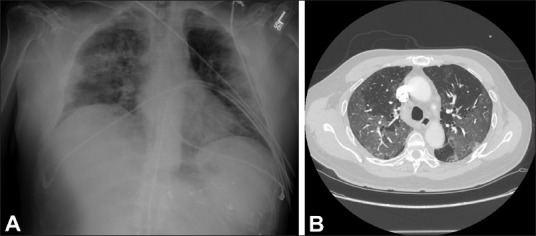

There seems to be a unique interplay between 2019 novel coronavirus (SARS-CoV-2) and cardiovascular diseases, although it is predominantly a respiratory illness. Patients with pre-existing cardiovascular co-morbidities appear to be at highest risk for mortality from coronavirus disease 2019 (COVID-19) along with the elderly; COVID-19 also contributes to cardiovascular complications, including acute coronary syndromes, arrhythmias, myocarditis, acute heart failure, and, in the most severe cases, cardiogenic shock and death. Several medications proposed in the treatment of COVID-19 require cardiac monitoring owing to their cardiac-specific adverse effects. Ultimately, the COVID-19 pandemic has jeopardized the safety of heart transplantation and has placed transplant recipients on immunosuppressive therapies at significant risk. In this article, the authors summarize the rapidly emerging data on the cardiovascular implications of SARS-CoV-2 and COVID-19.